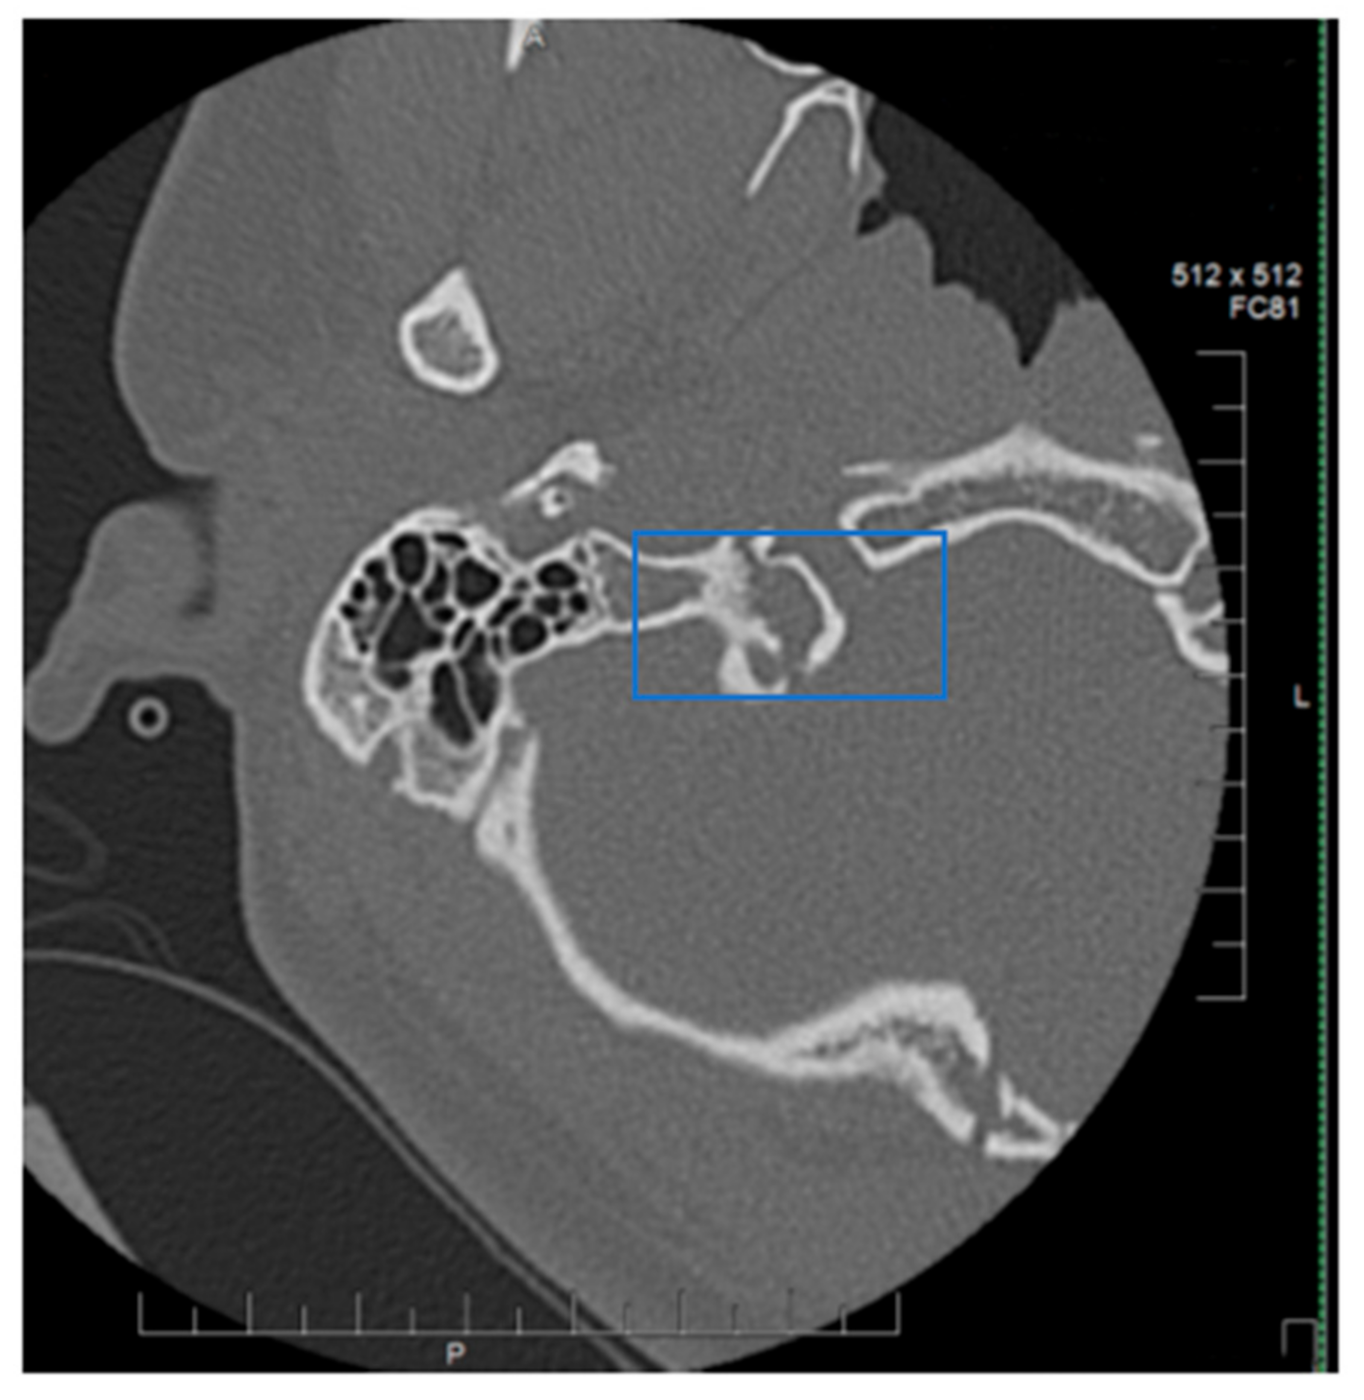

Collet–Sicard Syndrome has rarely been described as a consequence of blunt head trauma. Injuries to the jugular foramen and the hypoglossal canal are rare, as most blunt head traumas resulting in basilar skull fracture involve the condyles. In most cases, the condition is self-limiting, with patients regaining most to all of their neurological functions within 6 months. Several theories have been proposed for the pathophysiology of this syndrome. Displaced bony fragments that could compress the nerves in the context of fracture extension to the posterior jugular foramen or to the hypoglossal canal has been one theory to explain the neurological manifestations seen with CSS [6]. Bridgman et al. suggested that the cranial nerves were damaged by traction injuries [7]. Orbay et al. reported a case in which hypoglossal nerve palsy occurred 3 months after a head injury and suggested that a scarring process and the formation of a callus at the level of the hypoglossal canal could progressively compress the main hypoglossal nerve [8]. One of the more recent theories is that soft tissue edema, as a consequence of the local injury, compresses the cranial nerves (9, 10, 11 and 12) and leads to their deficits. With time, as the edema resolves, the neurological deficits also resolve [9]. The initial fracture, as can be seen by Figure 1, demonstrates a fracture on the border between the jugular foramen and the hypoglossal canal. CT of the Temporal bone better demonstrates the fracture location (See Figure 2). A subsequent MRI of the brain also demonstrates an area of hypo-attenuation, consistent with edema at the location of the jugular foramen and the hypoglossal canal (Figure 3). Treatment for CSS with blunt head trauma remains conservative, as other causes, such as a tumor or vascular impingement, require treatment of the underlying cause. As the edema resolves, so do neurological deficits. Some authors have advocated the anecdotal use of steroids to reduce the edema; however, as this case is very rare, large multi-institutional trials are warranted to better elucidate the role of steroids with Collet–Sicard syndrome. Of important note is to readily identify this condition and provide nutritional support with feeding tubes, as the recovery time is generally 3–6 months. In conclusion, injuries with focal neurological deficits which were not apparent on initial imaging should be reviewed by relevant experts with concomitant knowledge of the patient’s history and experience in neuroimaging.

Figure 2. CT temporal bone. Highlighted blue box indicates junction of Jugular foramen and Hypoglossal Canal.